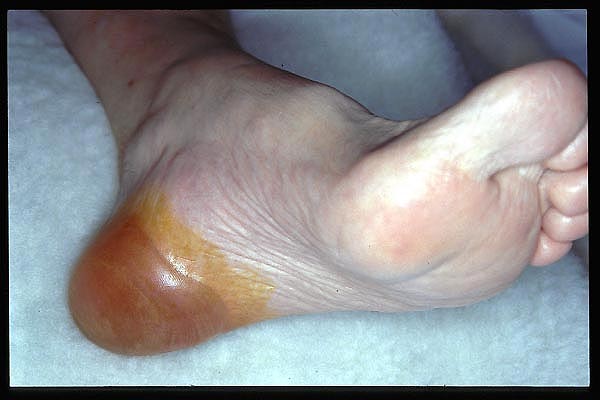

UPP 4º de talón con prominencia de calcáneo. Muy evolucionada.